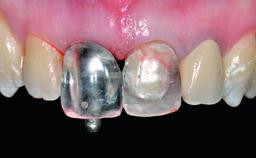

Replacement of a Missing Upper Left Central Incisor, Late Placement of an RC Bone Level Implant and Adjacent Tooth Restoration

A healthy 38-year-old male patient was referred for replacement of a failing tooth-supported cantilever fixed dental prosthesis on teeth 11 and 21. The patient reported a history of trauma at 13 years of age that had resulted in the subsequent loss of tooth 11, as well as endodontic treatment of the adjacent abutment tooth 21. A metal-ceramic cantilever fixed dental prosthesis replacing tooth 11 had been provided by his general dentist several years after the loss of the tooth, with tooth 21 as the sole abutment. At the time of initial presentation, this restoration had been in service for over 20 years.

Abutment Type Customized

Prosthesis Type FDP